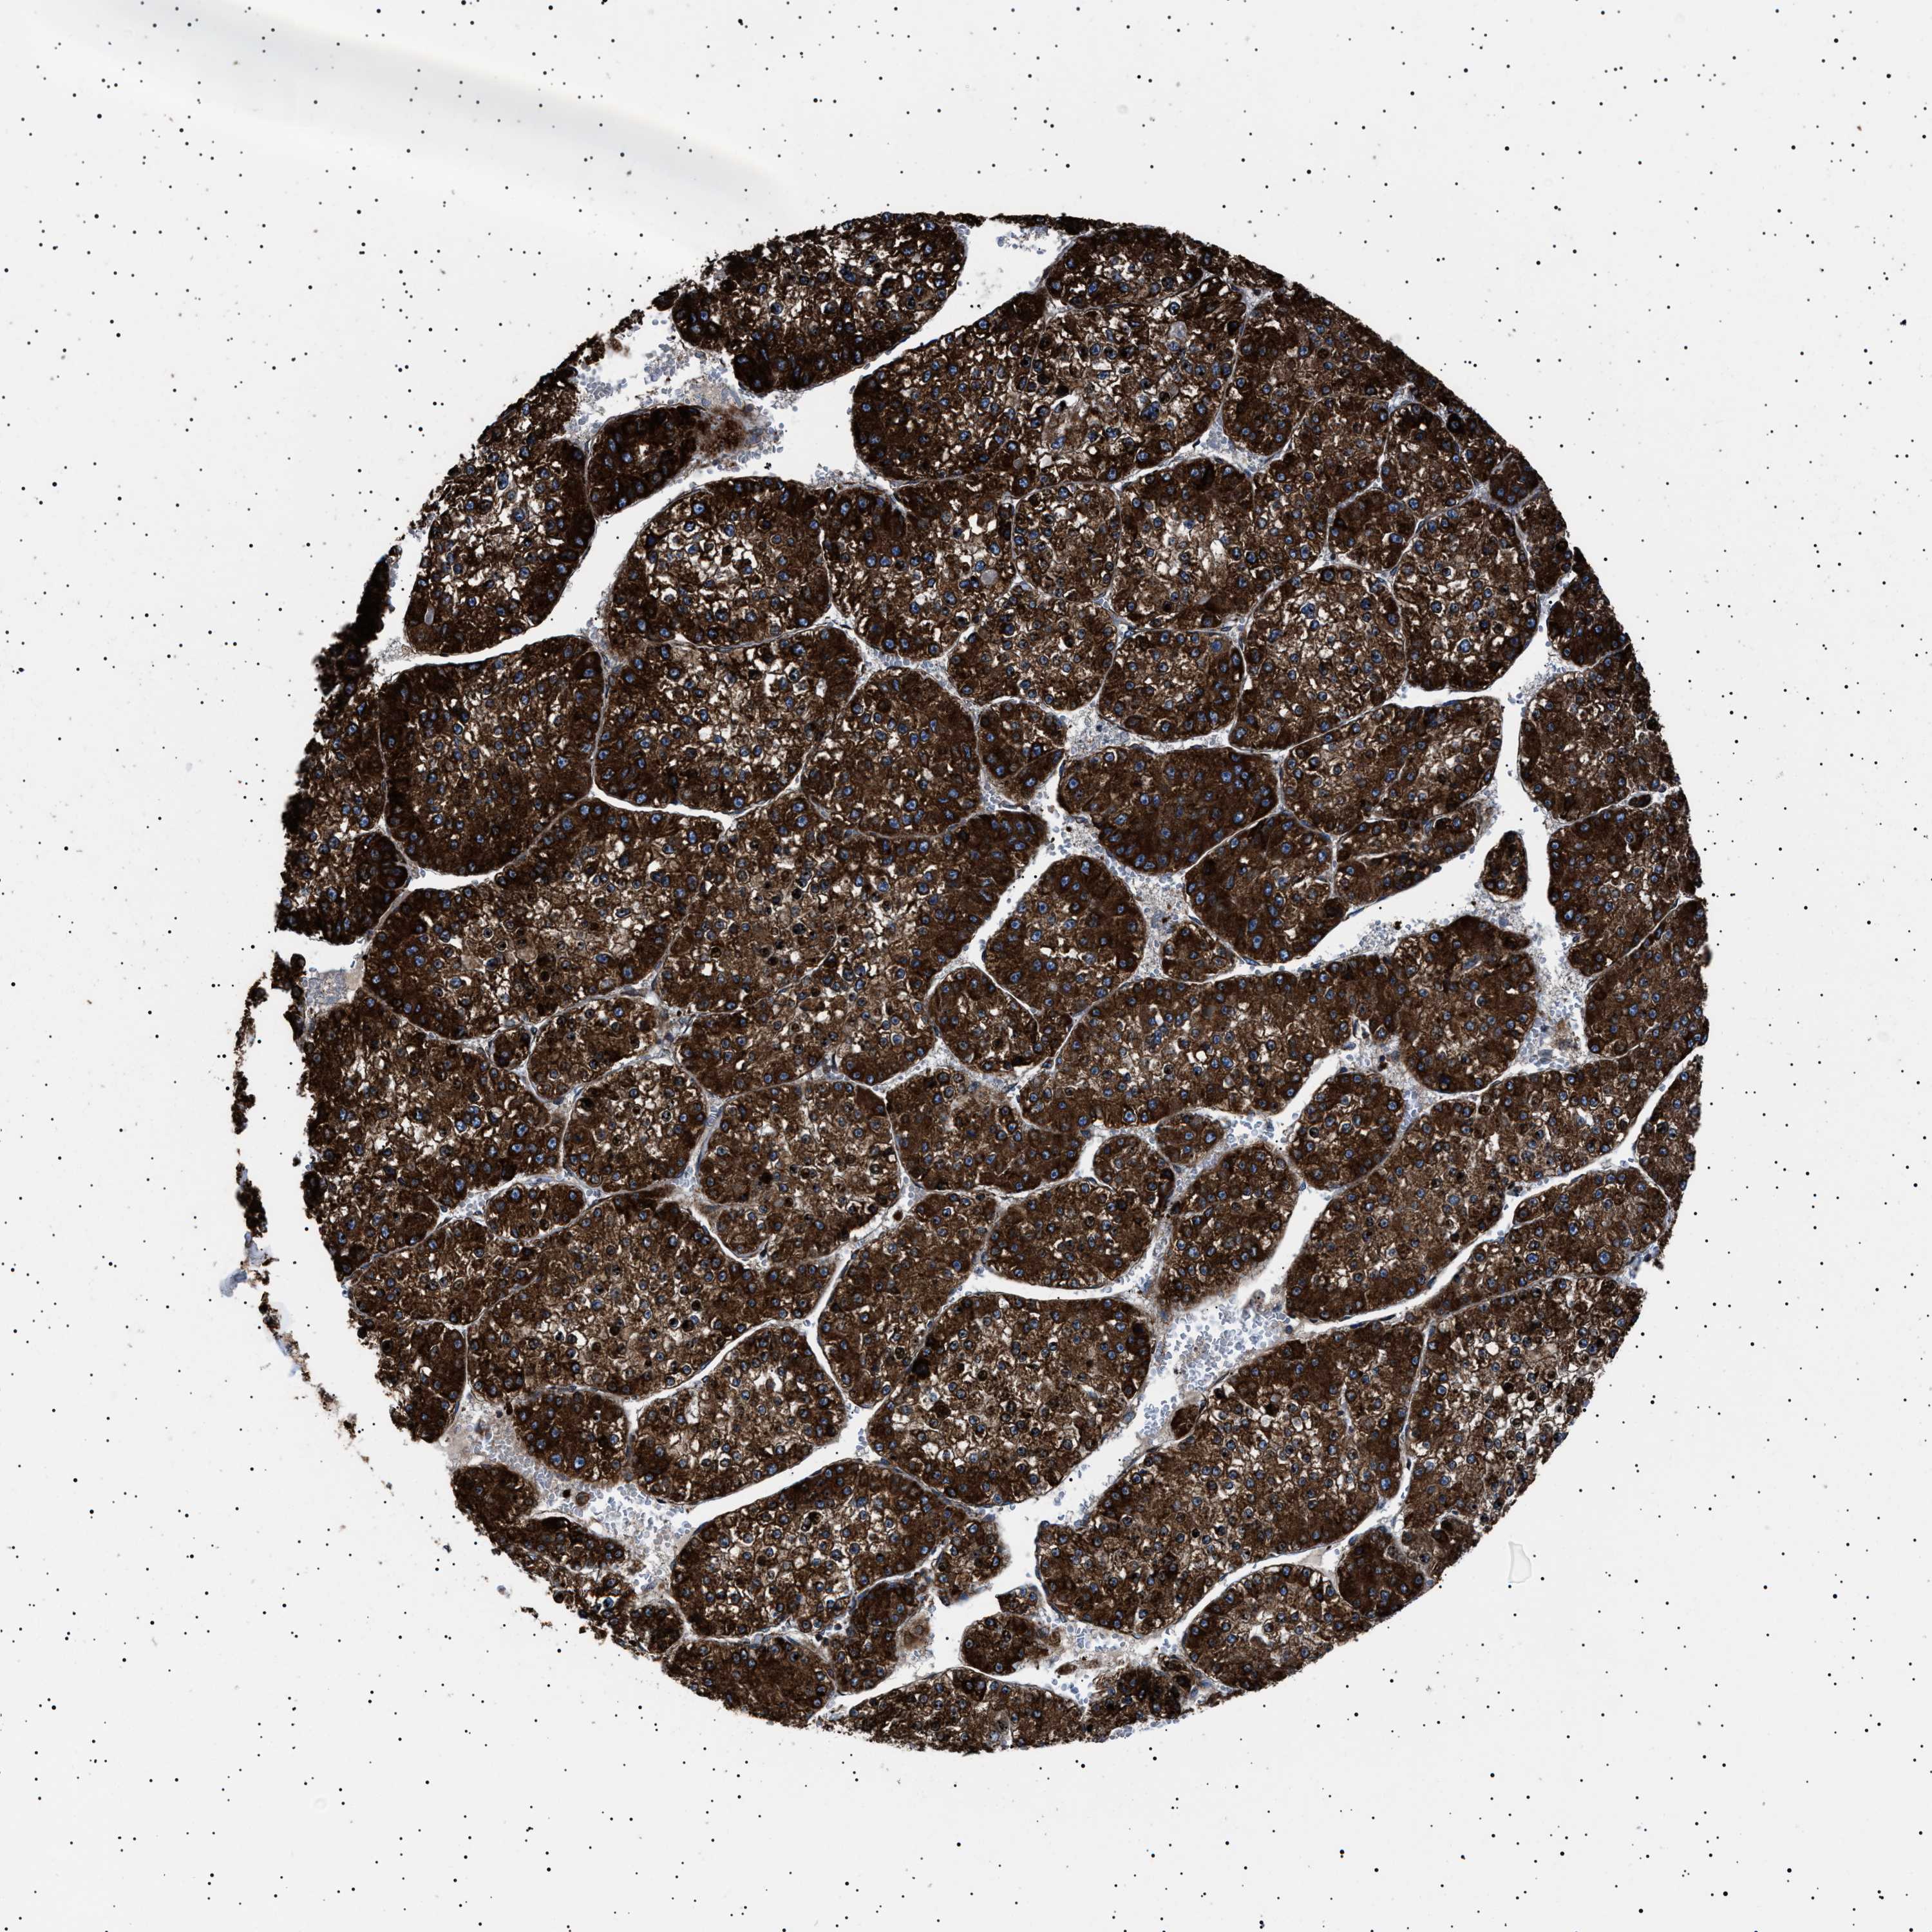

LIVER CANCER - Protein expressioni

A mouse-over function shows sample information and annotation data. Click on an image to view it in a full screen mode. Samples can be filtered based on level of antibody staining by selecting one or several of the following categories: high, medium, low and not detected. The assay and annotation is described here.

Note that samples used for immunohistochemistry by the Human Protein Atlas do not correspond to samples in the TCGA dataset.

Antibody stainingi

Antibody staining in the annotated cell types in the current human tissue is reported as not detected, low, medium, or high, based on conventional immunohistochemistry profiling in selected tissues. This score is based on the combination of the staining intensity and fraction of stained cells.

Each image is clickable and will lead to virtual microscopy that enables deeper exploration of all samples and also displays staining intensity scores, fraction scores and subcellular localization as well as patient and tissue information for each sample.

Antibody HPA001915

Antibody HPA021542

Staining

High

Medium

Low

Not detected

Intensity

Strong

Moderate

Weak

Negative

Quantity

>75%

75%-25%

<25%

None

Location

Nuclear

Cytoplasmic/membranous

Cytoplasmic/membranous,nuclear

Cholangiocarcinoma

Carcinoma, Hepatocellular, NOS